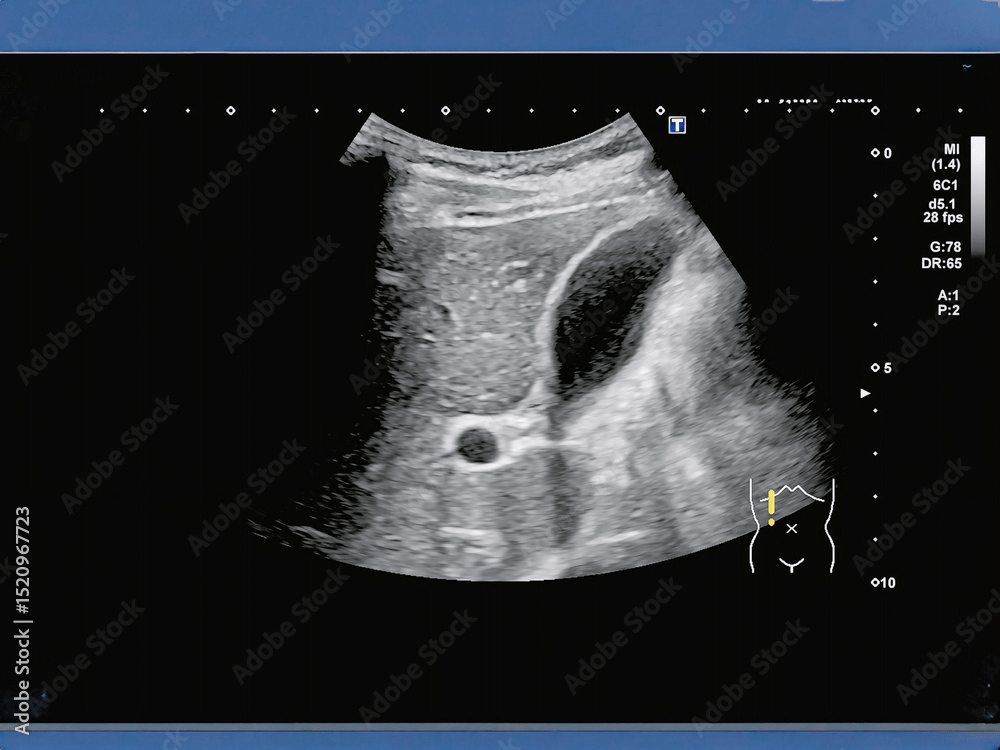

腹部超音波検査は、超音波を使ってお腹の中の臓器を観察する検査です。

- 肝臓:脂肪肝、肝炎、腫瘍などの確認

- 胆のう・胆管:結石やポリープ、炎症の有無

- 膵臓:腫瘍や炎症の有無

- 腎臓:結石、腫瘍、腫れなど

- 脾臓:大きさや腫瘍、血流の状態

- 大動脈:瘤(こぶ)の有無

- 膀胱:腫瘍、結石、残尿量